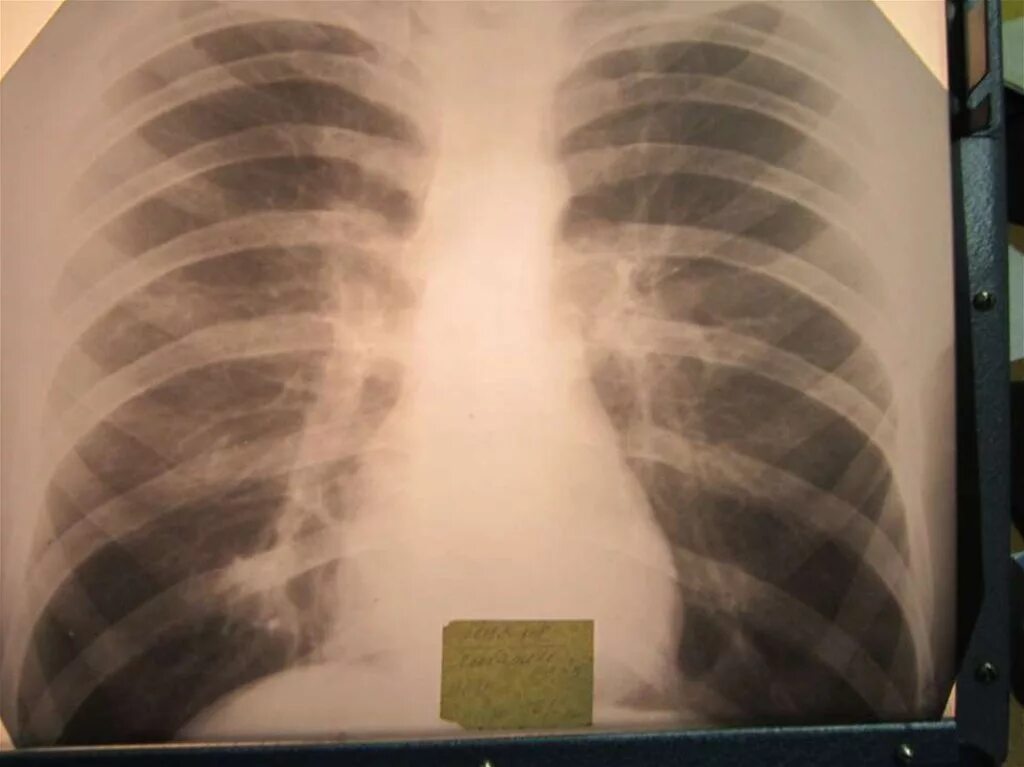

Бронхоаденит это